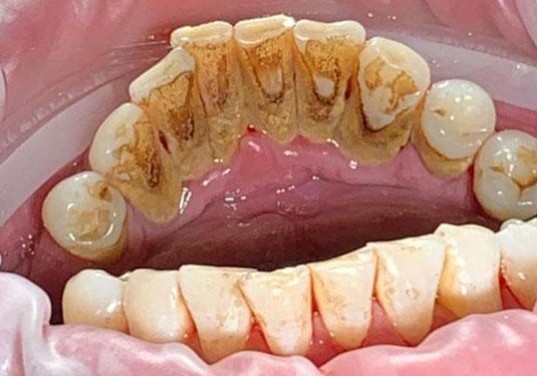

На странице представлено портфолио стоматологий Москвы с работами до и после профессиональной чистки зубов. В нашем портфолио собраны разные клинические случаи: от удаления незначительного налета до снятия массивного поддесневого камня. Здесь вы можете увидеть, как возвращается естественный цвет и внешний вид зубов после процедуры. Изучите результаты до и после чистки зубов, чтобы увидеть реальный эффект и выбрать клинику в Москве, где профессиональная гигиена поможет вернуть зубам здоровый вид.

Профгигиена

Пациентке провели профгигиену зубов и полости рта и выровняли края зубов в зоне улыбки